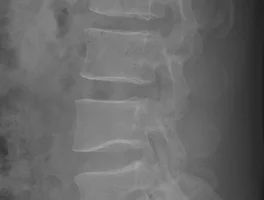

| 압박골절 장해등급 심사청구 및 재심사청구 (0) | 2019.04.08 |

| 장애등급기준 척추압박골절 산재장애등급 급여 (0) | 2017.01.19 |